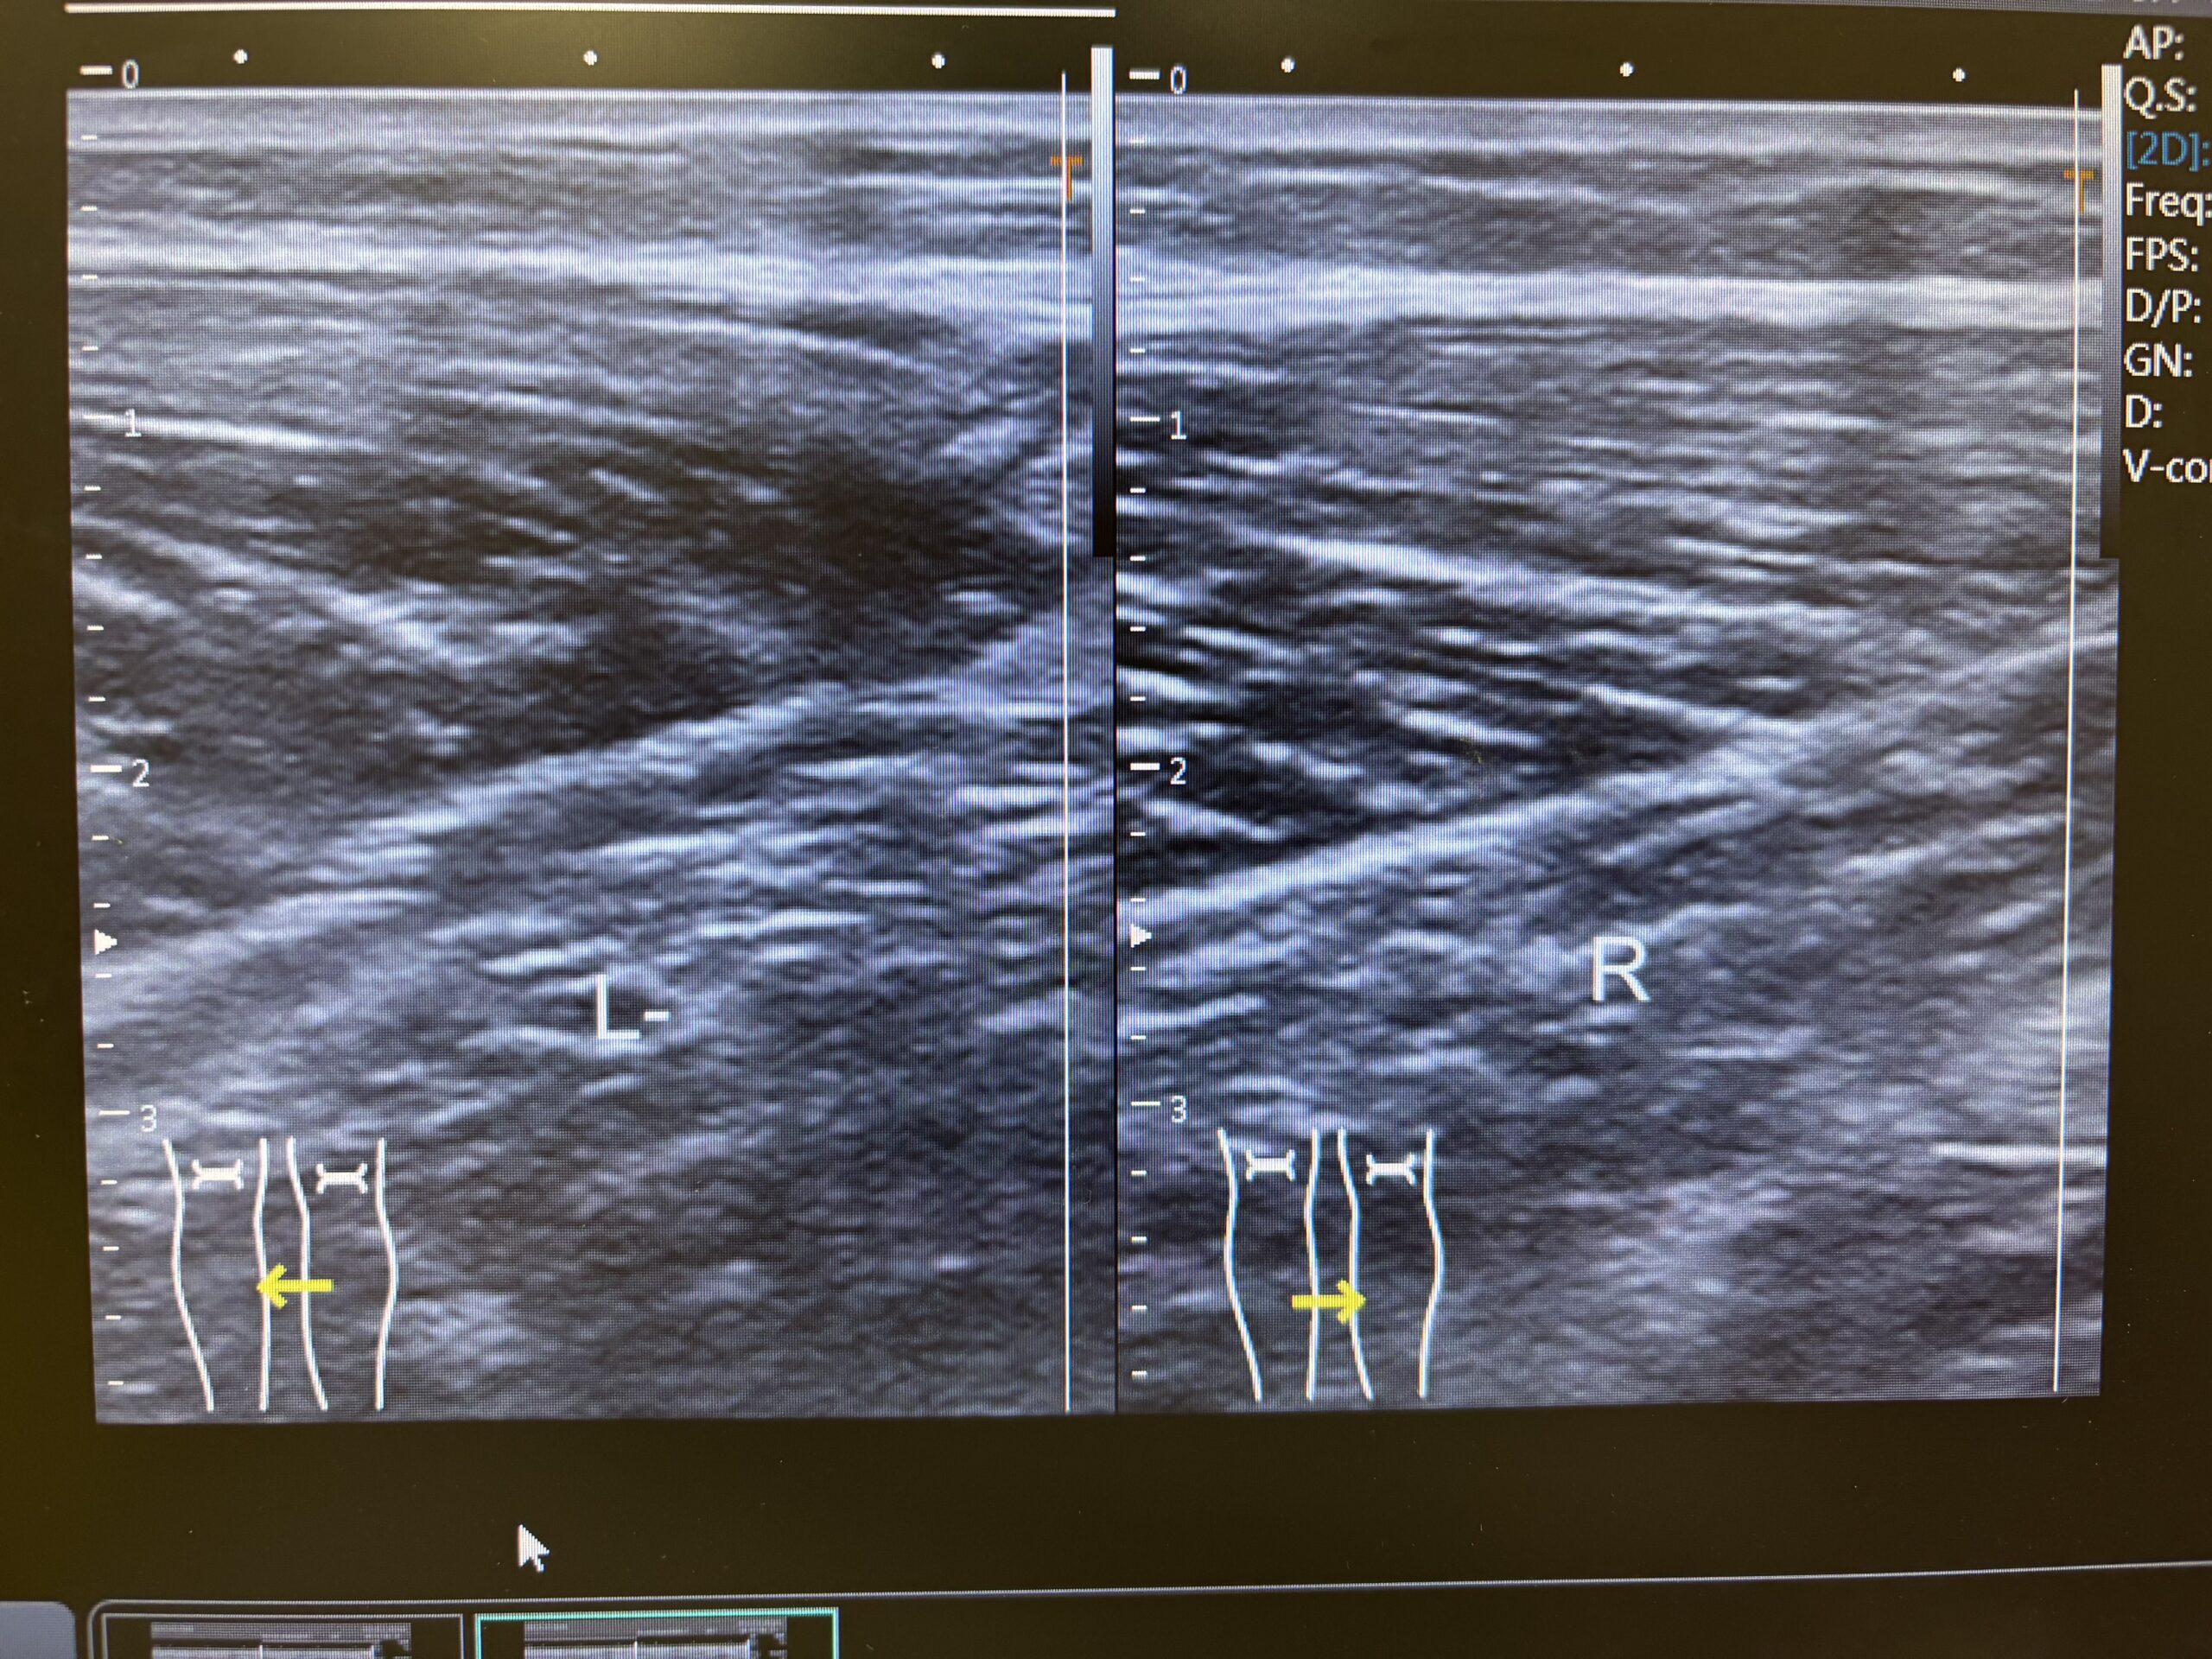

介護の仕事中、階段で人を支えようとした際に負傷。熱感、圧痛あり。歩行時痛(+)エコーにて炎症反応確認。

労災適応で治療

電気療法【TENS(疼痛緩和)、MCR(組織修復)、干渉波 】、超音波治療、運動療法

1週間は、電気療法(TENS、MCR)、超音波

以降は、電気療法(干渉波)、超音波、運動療法

3週間後、完治